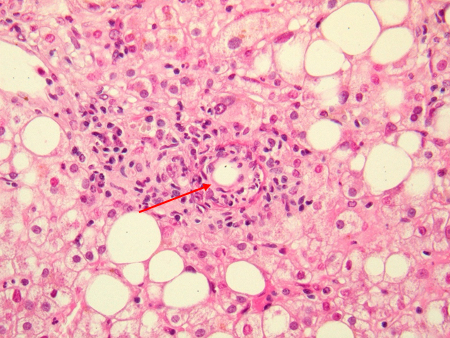

Liver "doughnut granuloma" characteristic of acute Coxiella burnetii hepatitis. Note the specific granuloma morphology as a doughnut. No bacteria may be seen in this granuloma

Hubert Lepidi, Institut Hospitalo-Universitaire Méditerranée Infection